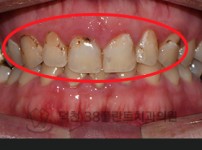

치료전후